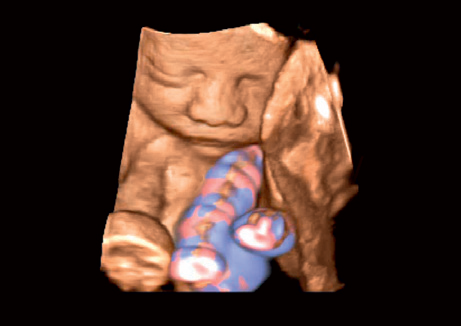

Режимы визуализации Canon (Toshiba) Aplio 300

B, M, PWD, CWD, ЦДК, THI, 4D, динамический поток (Dynamic Flow), энергетический доплер (Power), контрастная эхография (CHI 2D) и комбинированные режимы, включая следующие: B/M, B/PWD, BDF/PDW, BDF/MDF,BDF/MDF/PWD, 2D/CWD, BDF/CWD (BDF-режим изображения, в котором CFM изображение накладывается на B-режим изображения, MDF-режим изображения, в котором CFM изображение накладывается на M-режим изображения)

• 3D Color - цветное 3-х мерное изображение

• STIC Color - цветная объёмная визуализация сердца плода

• Трехмерная эхография в реальном времени с использованием специализированных 4D датчиков;

• Программа анализа сердца плода в трех проекциях в реальном времени 4D Stick;